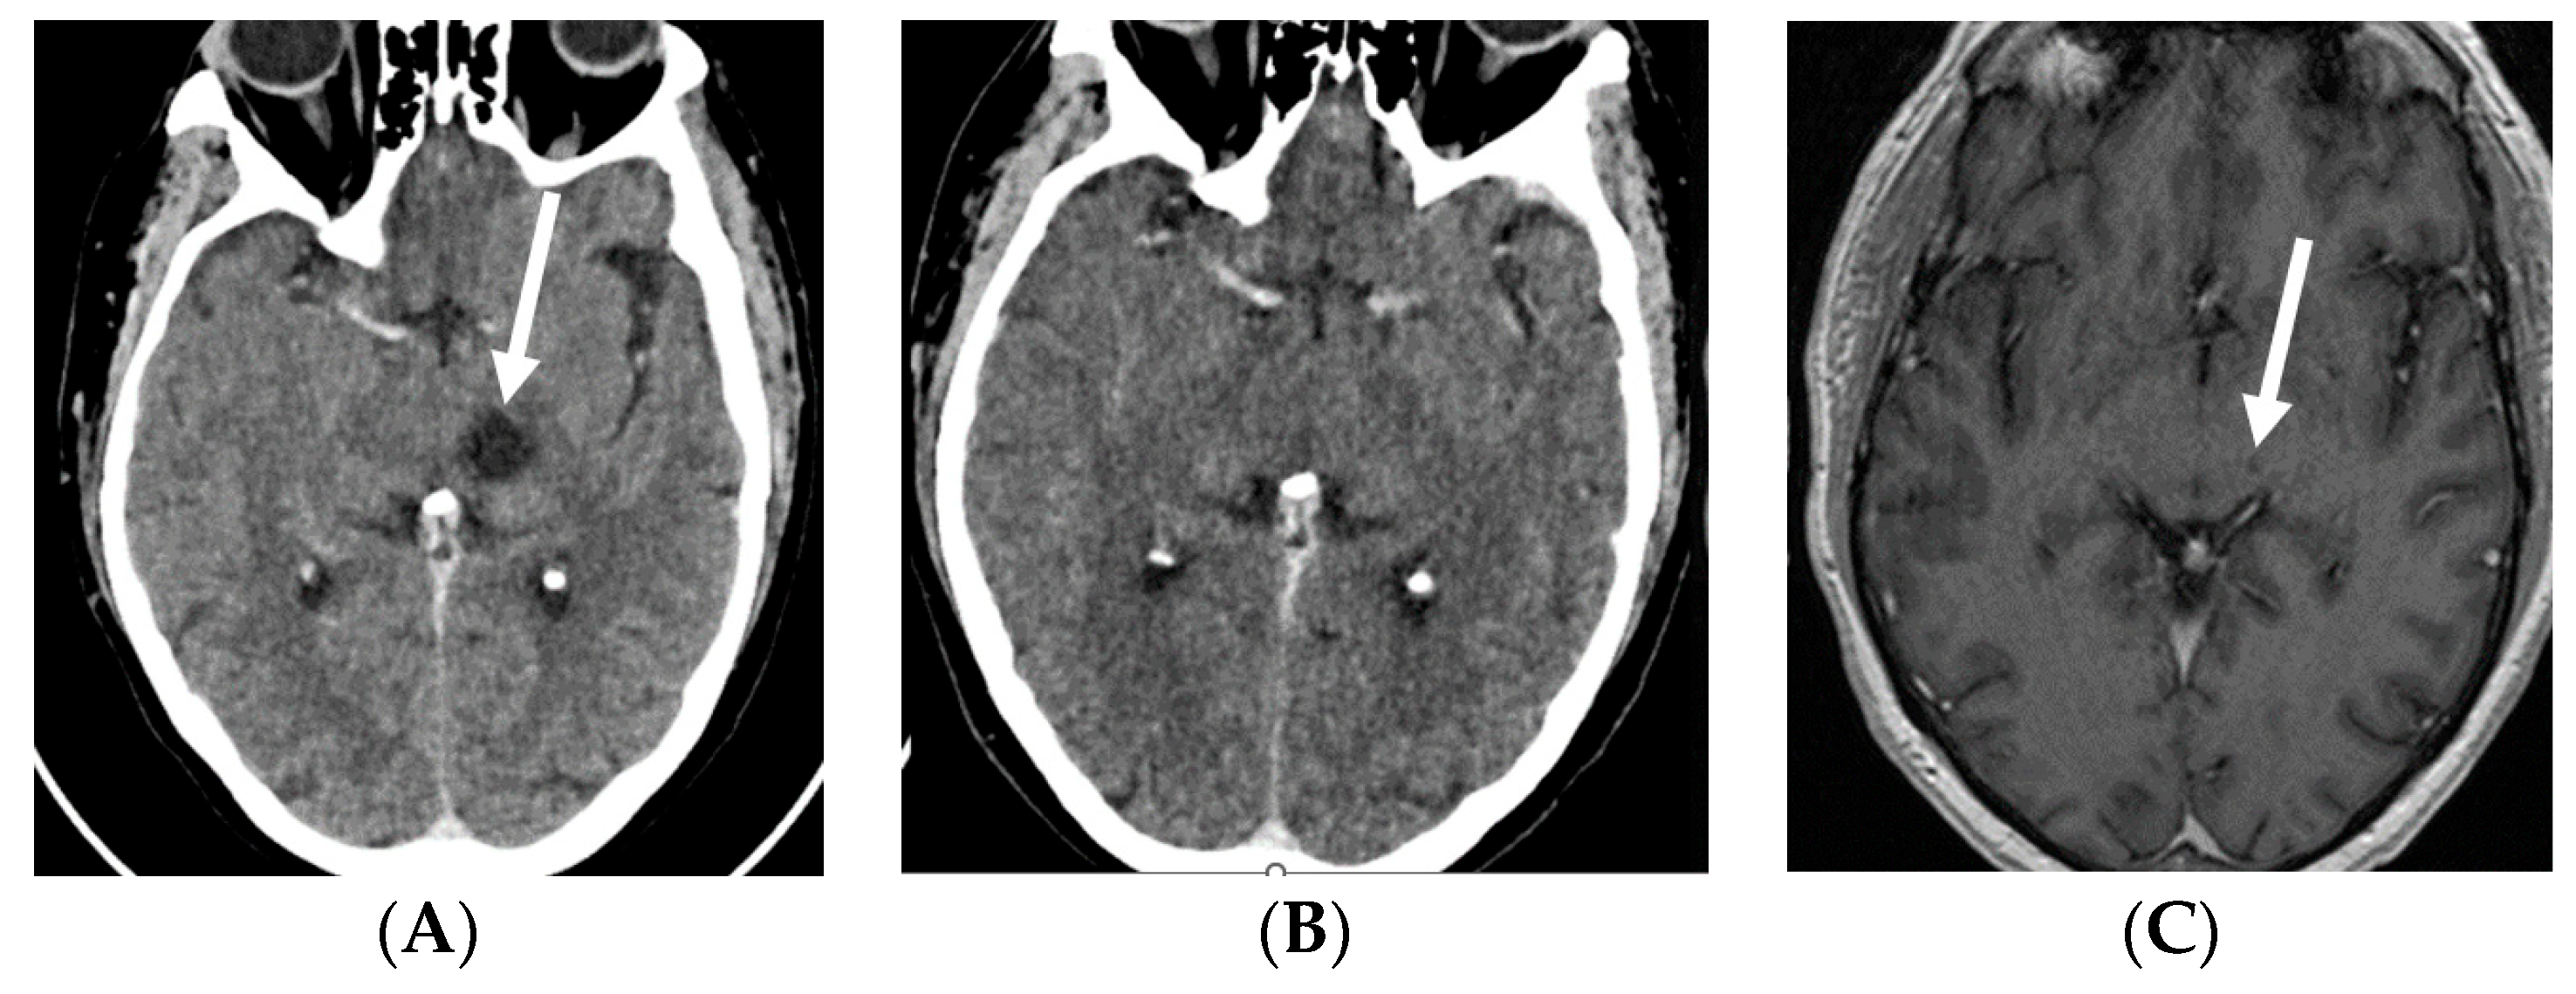

2.1. Case 1